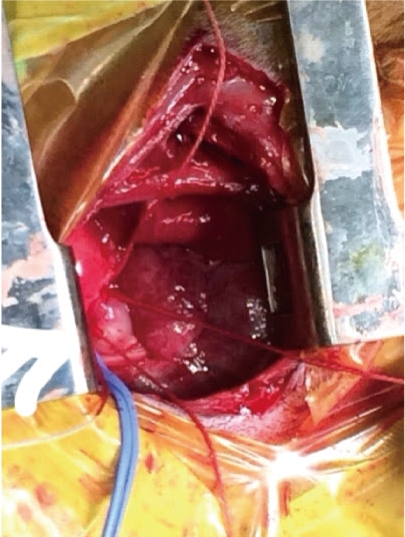

【圖十三】以擴胸器將第五肋間撐開 穿線處即是愈結紮的PDA導管